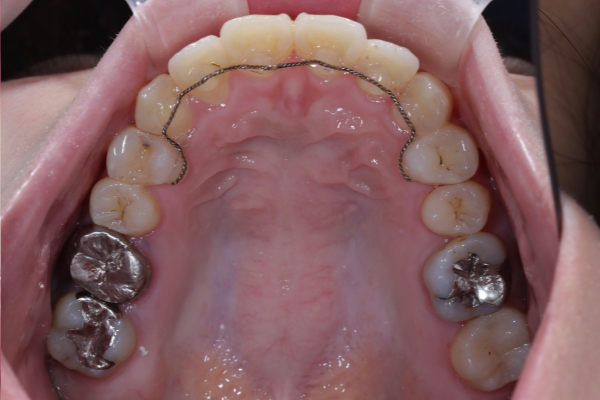

埋まっている犬歯の牽引

残存していた乳犬歯を抜歯後、埋伏している上顎犬歯に対して外科的開窓を行い、矯正装置を用いた牽引を開始しました。

歯列に大きな叢生が認められなかったため、全体的な歯列バランスを維持しながら、スペース管理を行い慎重に犬歯の誘導を進めました。

定期的に歯の移動方向や歯周組織の状態を確認しながら治療を行いました。

本症例では適切なタイミングで診断と介入を行えたことで、矯正的牽引により永久犬歯を歯列内へ誘導することができました。

犬歯は咬合誘導および審美性に重要な役割を担う歯であり、早期の診断が将来的な咬合安定につながります。